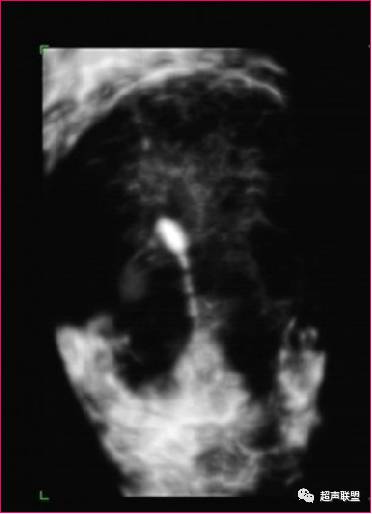

圆形环

由于宫内节育器的形状、质地不同,其超声表现不尽相同。金属圆环和宫形环在二维超声扫查子宫纵切面表现为宫腔内两个分离的强回声,在其后方,由于产生多次反射形成慧尾征。T形环在子宫纵切面显示为宫腔内线状或串珠状强回声,横切面在宫腔底部显示条形强回声,塑料节育器在不同的切面扫查进表现为宫腔内强回声,其后方不伴慧尾征。

子宫纵断面,在宫腔内显示明亮强回声的IUDIUD断面呈二字形或一字形短条状,前倾曲及后倾曲子宫内的节育环因为与声束垂直而呈环状强回声,周围有声晕,即使降低增益仍能显示IUD回声。如有次序的连续纵断IUD,各断面可组成“O”形图像。二字形强回声平面联机与宫体纵断面平行。